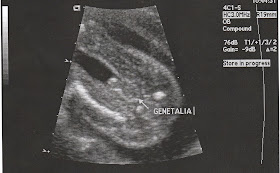

This was Chris' 'that's my kid! moment'....

Yep, it's a BOY!!!! It was the first pregnancy that even I could make it out before the tech told us. I said, "It's a boy!" The tech said, "Yeah, there's NO missing that." Then I quietly marvelled at Chris' restraint and silence, since I knew he was thinking proudly, "That's my boy!"